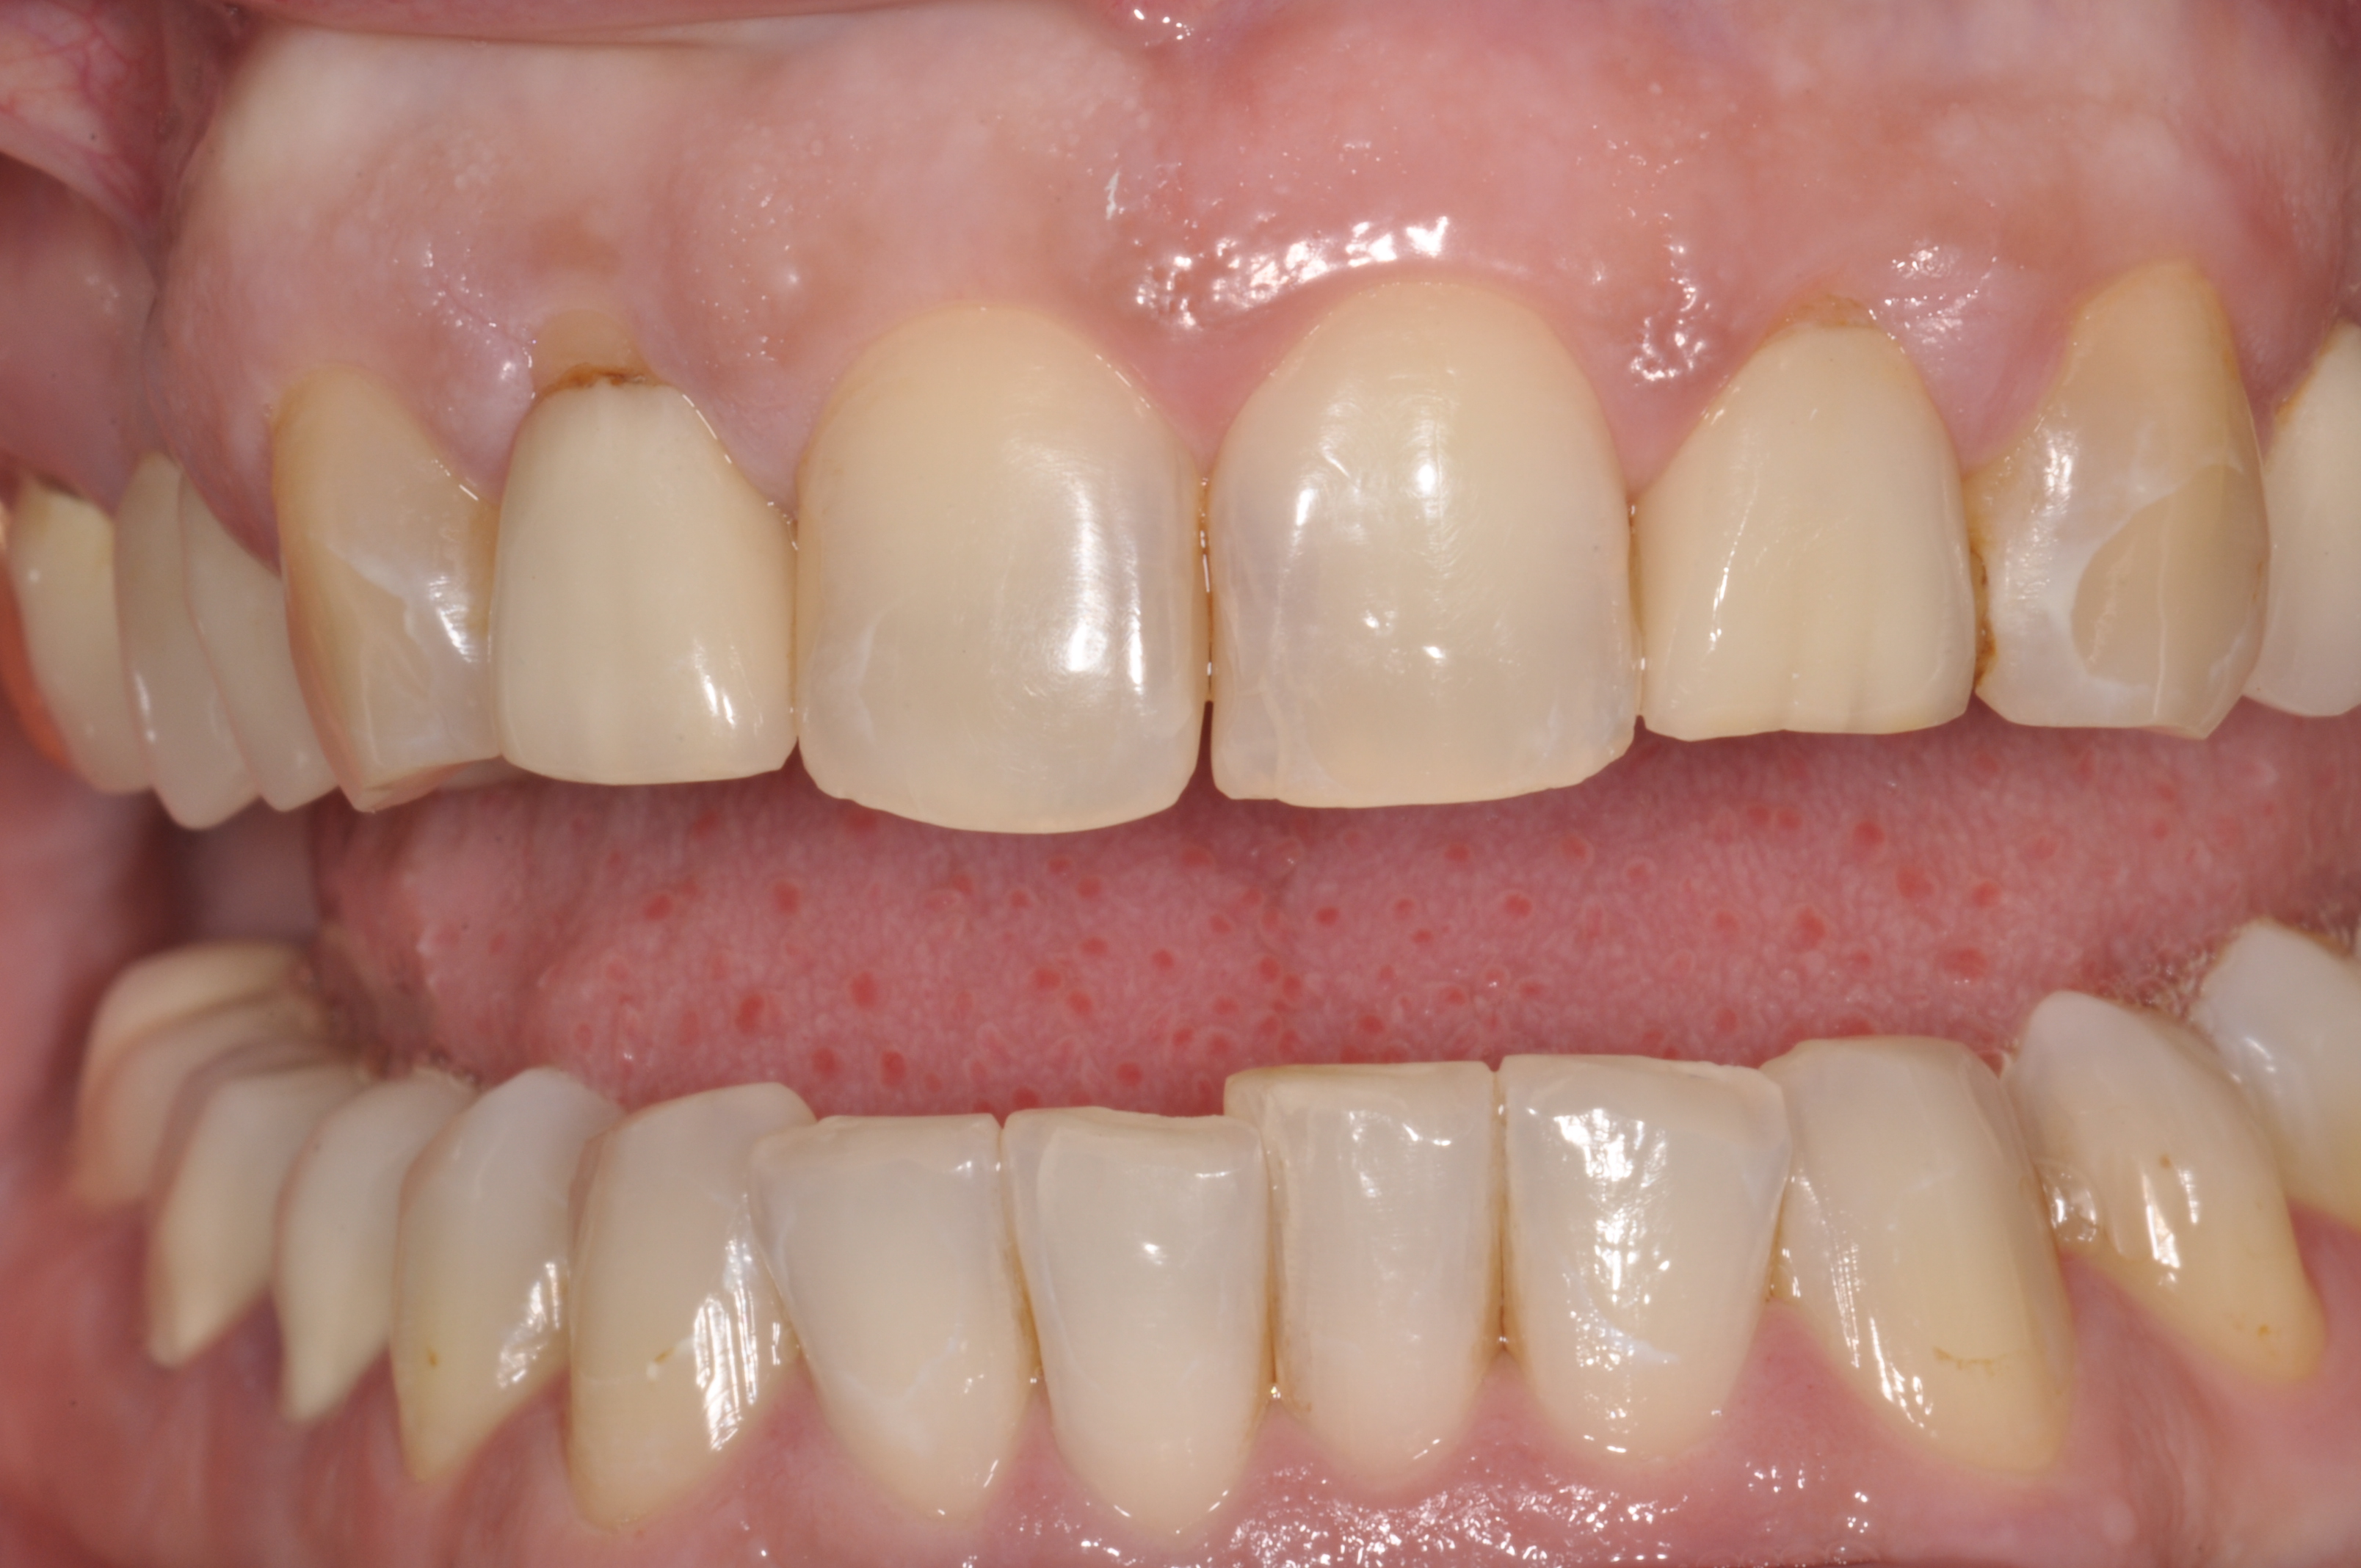

Gesamtbehandlung in Sedierung: die Seitenzähne wurden durch Keramik-Implantate (Zahnentfernungen und Sofortimplantation) mit Knochenaufbau ersetzt; anschließend Gesamtüberkronung aus Vollkeramik mit Optimierung der Ästhetik

Nachher: Gesamtbehandlung in Sedierung: die Seitenzähne wurden durch Keramik-Implantate (Zahnentfernungen und Sofortimplantation) mit Knochenaufbau ersetzt; anschließend Gesamtüberkronung aus Vollkeramik mit Optimierung der Ästhetik